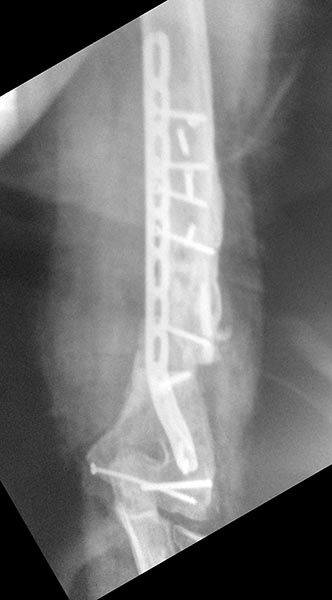

Уважаемые коллеги, хотелось бы услышать вашего мнения по поводу

непростого случая несросшегося перелома плечевой кости.

Пациент 44года в 2013г закрытый многооскольчатый перелом дистального

отдела правой плечевой кости. Остеосинтез пластинами в одной из

цифры).В августе 2015г удаление металлофиксаторов, невролиз лучевого

нерва, реостеосинтез (той же) пластиной, но в положеном

задне-латеральном положении.

Неделю назад пациент стал говорить что появился хрукт. Рентген контроль

- перелом 2х винтов нестабильность вторичное смещение.

Предварительно планирую брать на ревизию удалить винты с проксимального

отдела, репозиция остеосинтез и дополнительно медиальная

реконструктивная? пластина.

Вопросы: 1 брать сейчас или ждать закрытия дефекта кожи?

2 Ставить ли промывную систему? Не увеличится ли риск инфицирования,

если 3 раз та же пластина?